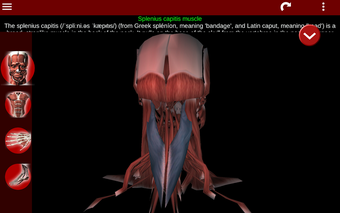

Esta herramienta educativa proporciona una descripción de cada músculo del cuerpo humano, así como un modelo tridimensional del sistema muscular. Con sólo tocar con el dedo, la aplicación revelará la información pertinente.

Los usuarios pueden hacer zoom sobre el músculo, así como elegir si ocultar o mostrar los datos. La orientación puede ser horizontal o vertical, según convenga más.